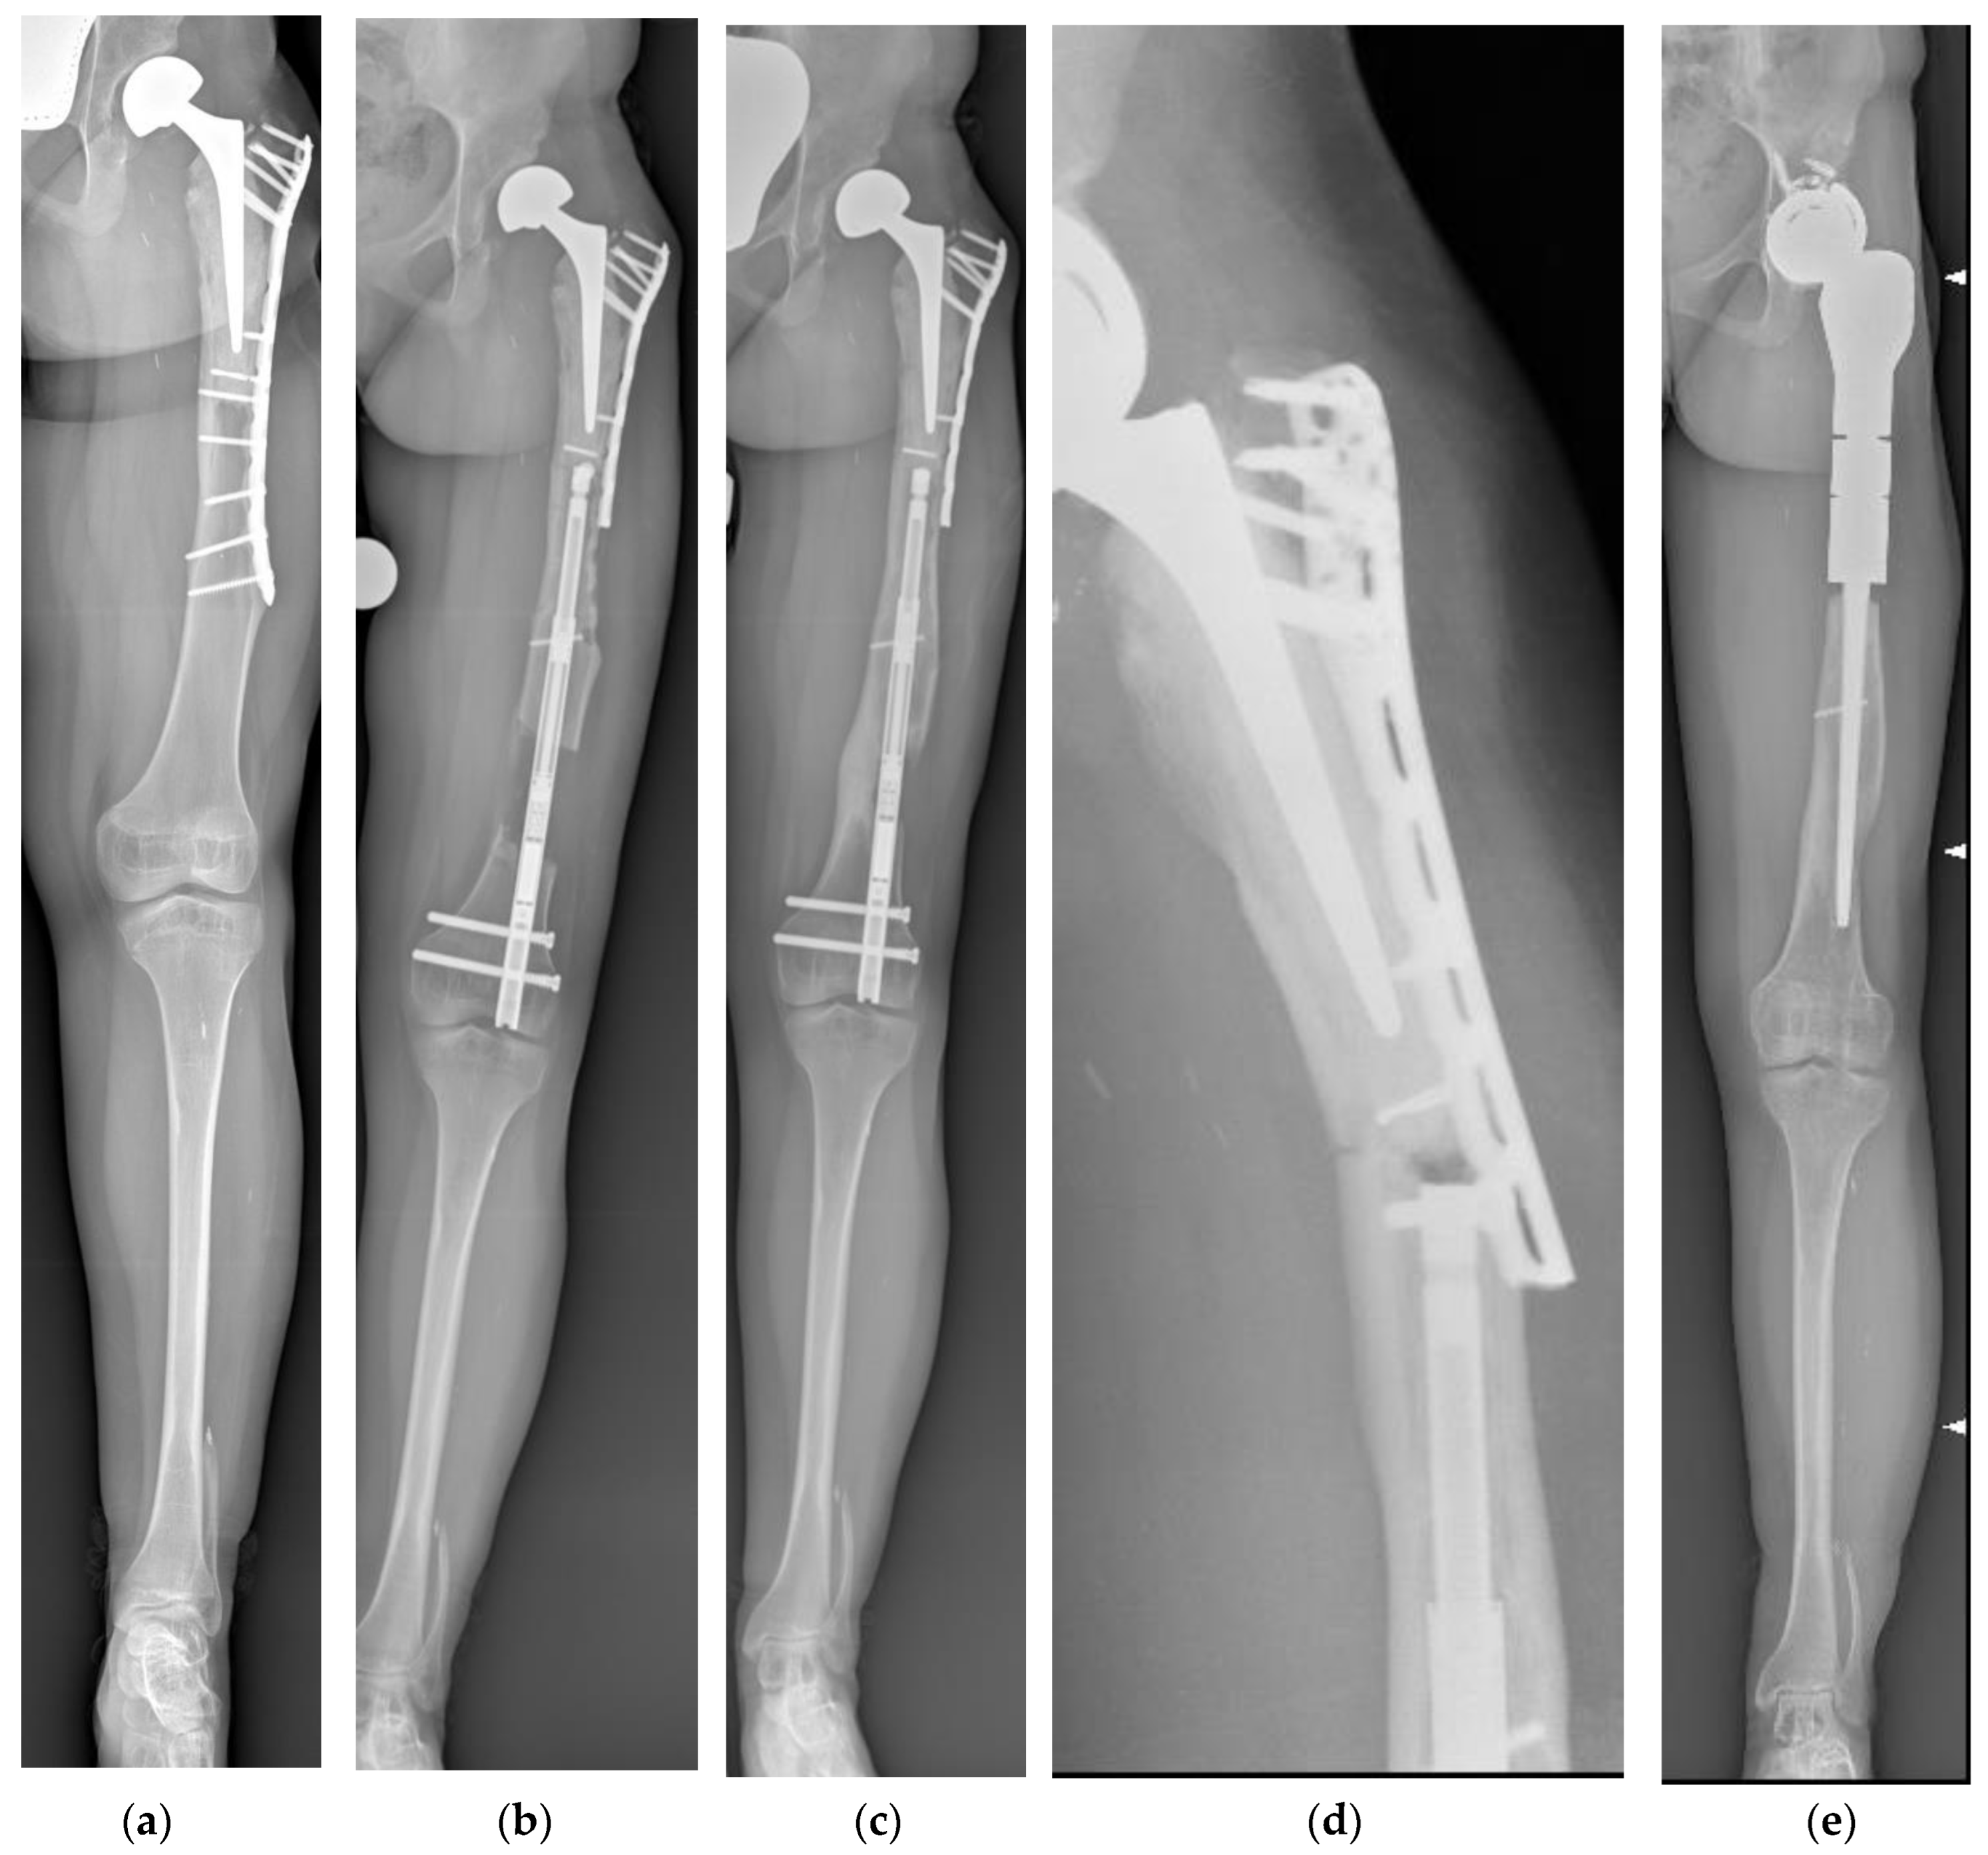

Figure 2.

(a) Antero-posterior panoramic lower limb radiography of a 15-year-old female patient treated for left proximal femur osteosarcoma when she was 4 years old. She underwent proximal femur composite endoprosthesis. The achieved LLD was 5 cm. The available space for the nail was only 19 cm, while the shortest one was 215 mm. We had to cut 1 cm off of the telescopic part of the nail to minimize the protrusion as much as possible. The patient did not mention pain during knee extension or flexion. (b) Antero-posterior panoramic lower limb radiography showing hip endoprosthesis subluxation during lengthening. Lengthening was performed as scheduled until the end of lengthening. (c) During the consolidation phase, the running back phenomenon was observed, and the nail was shortened by 1 cm. Complete bone healing was observed 6 months after the end of lengthening. (d) Three years after the end of lengthening, the patient experienced a fracture proximally to the femur and reconstruction with a composite endoprosthesis, and (e) a proximal femur megaprosthesis was implanted.

One femur fractured proximally to the nail 36 months after the end of lengthening. The patient was previously treated with a proximal femur resection and reconstruction with a composite endoprosthesis. After the fracture, the previous reconstruction was removed, and a proximal femur megaprosthesis was implanted. A case of 1 cm nail shortening during the consolidation phase was observed (Figure 2).

In patients with a history of bone resection and reconstruction for bone tumors, the previous treatment impacts the lengthening strategy as well as the site of nail insertion, the nail size (diameter and length), the osteotomy seat, and whether the previous synthesis may need any changes. One patient experienced the running back (RB) phenomenon, hip subluxation, and a fracture proximally to the nail. RB consists of an acute shortening of the device and the regenerate. It may or may not be associated with the breakage of the rotation coupling of the nail, resulting in rotational instability. This is a well-known complication in PRECICE 2 nails and also affects other mechanical devices [23,31,43,44]. In our RB case, we observed only shortening without any rotational instability. The patient had previously been treated with a proximal femur composite endoprosthesis when she was 6 years old. Lengthening was performed 8 years later, and subluxation was expected from the beginning of lengthening. Acetabulum resurfacing was planned and performed 1 year after the end of lengthening. These data are consistent with previous studies. Wagner et al. [27] described 1 out of 32 patients, and Szymczuk et al. [45] described 2 cases in a series of 30 nails; other studies include [17,23,46].

The same patient experienced a fracture between the nail and the previous reconstruction. To perform intramedullary lengthening, we decided to remove the screws and shorten the plate in hopes of avoiding any mechanical interference during nail insertion. A retrograde femoral nail was used, the osteotomy was performed distally to the femur, and the nail was proximally fixed in the allograft. Plate shortening had increased the stress in the transition area between the nail and the previous reconstruction, leading to the fracture. Shortening hardware provides limited benefits. In patients with a comparable reconstruction, lengthening was successfully performed without plate shortening. In other words, the surgeon must preserve the first reconstruction as much as possible and avoid a stress riser by leaving unprotected bone. To the best of our knowledge, this has never been addressed in the literature thus far.